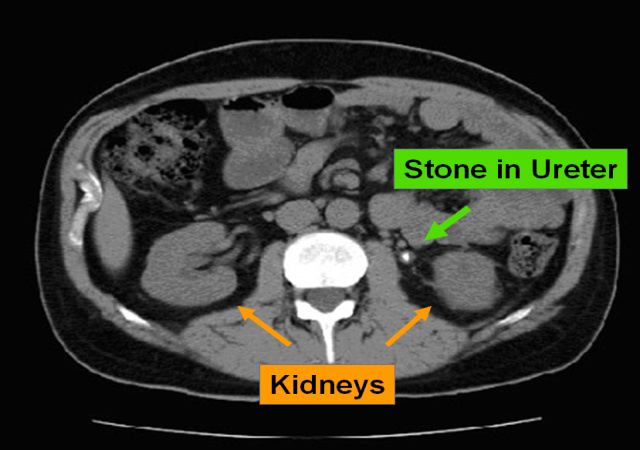

CT scan

CT scan showing proximal left ureteral stone